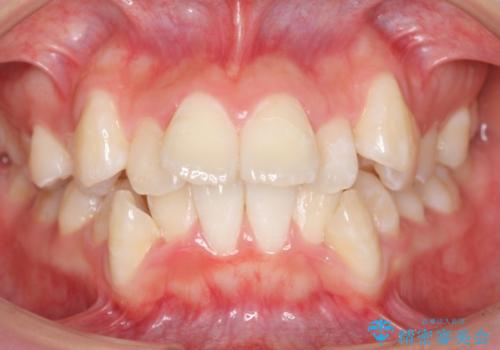

矮小歯 インビザラインとセラミックで美しく

- 前歯のがたつきと小さな歯の形を治したいと来院。

前から2番目の歯が小さく、細くとがった形になっていました。

大きくしようにも、幅が少ない上に、また、内側に入ってしまっているため、矯正治療で前歯を並べてからセラミックでかぶせることにしました。

いきなりセラミックでかぶせるよりも手間をかけた分、自然な仕上がりになっています。

先に矯正治療をすることで、下の前歯を内側に入れることができ、上の歯のセラミックの幅や厚みを取ることができました。